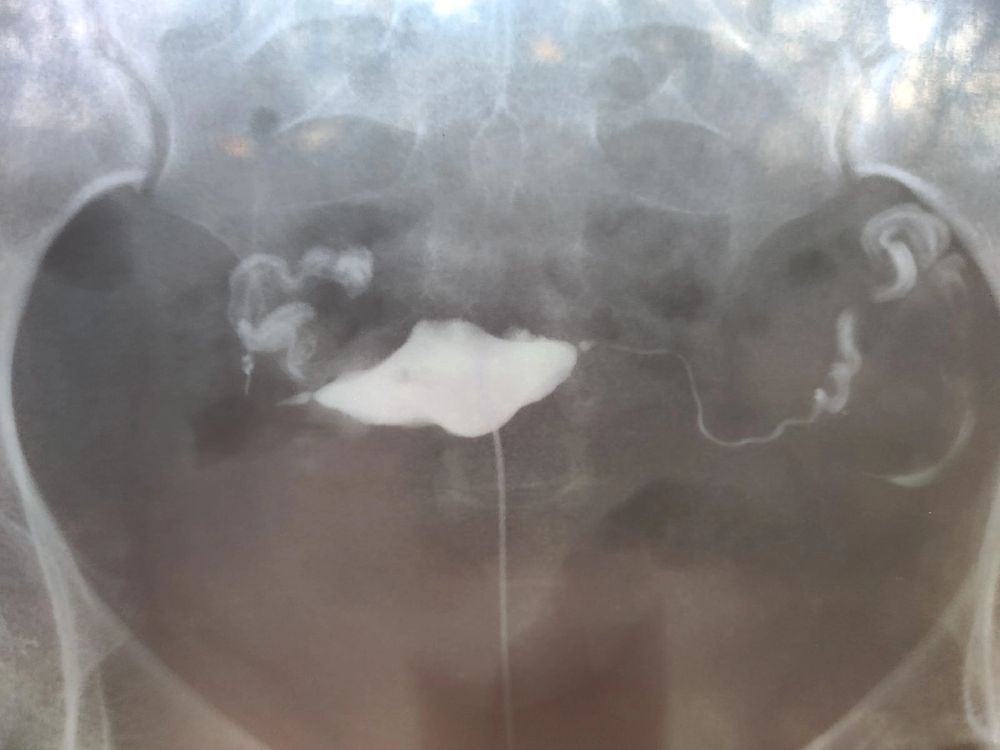

3. На гсг (проверке проходимости маточных труб) врач удивился, как такие трубы могут быть в 25 лет. Трубы сильно извитые , без пристальтики (тонуса) в них, то есть нефункциональны. Но оказались проходимы при введении в них йода. Так же были обнаружены спайки. Выяснили, что трубы стали такими вследствие перенесенного когда-то хламидиоза, о котором я даже не подозревала. В мазке ничего не определяется , об этом узнали по ИФА анализу крови.

Прикрепила рентген снимки труб и заключение по ним.